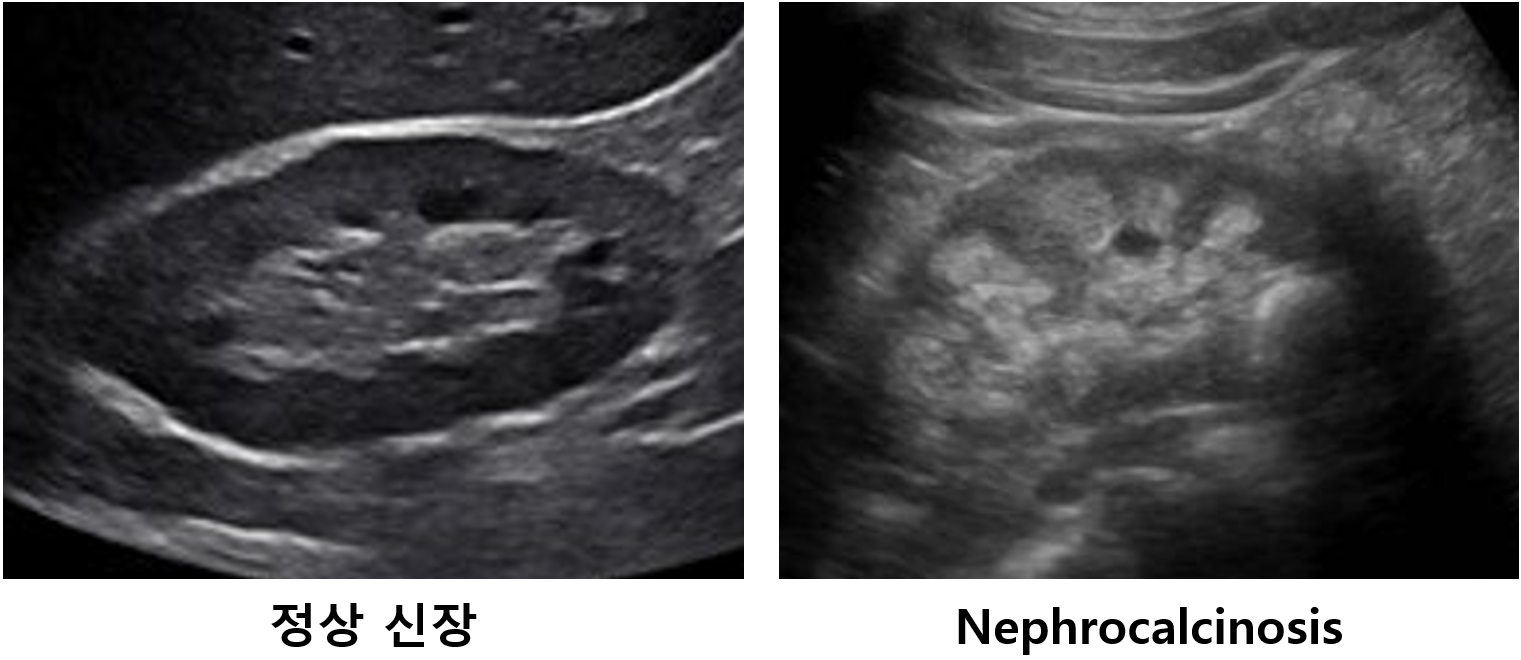

(3) Hypercalciuria: Alkaline urine으로 인해 발생 → 소변 내 Ca2+ 증가로 인해 요로결석, 골질환 등 동반